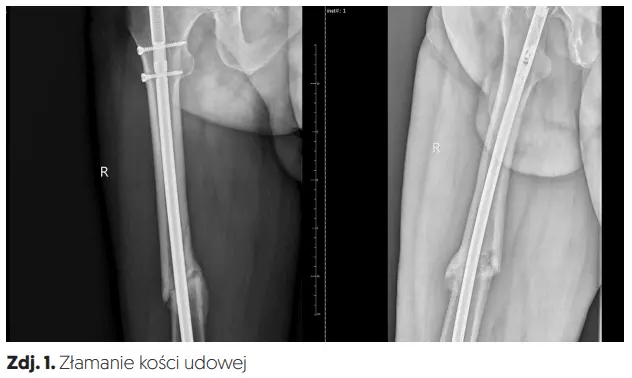

Złamanie trzonu kości udowej najczęściej wymaga leczenia chirurgicznego polegającego na zespoleniu określonych elementów kostnych np. płytką lub gwoździem śródszpikowym (zdj. 1, 2).